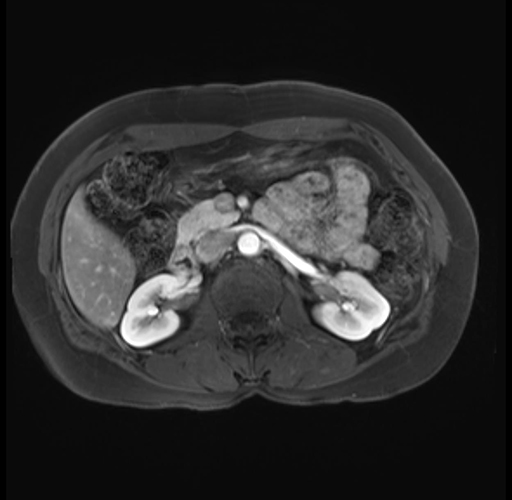

Imaging Analysis

Look through the patient's CT scan to identify any areas of concern for the necessary procedure.

Based on your CT findings, which issue(s) are present and would give reason for "planned slowing down moment(s)" in this case?